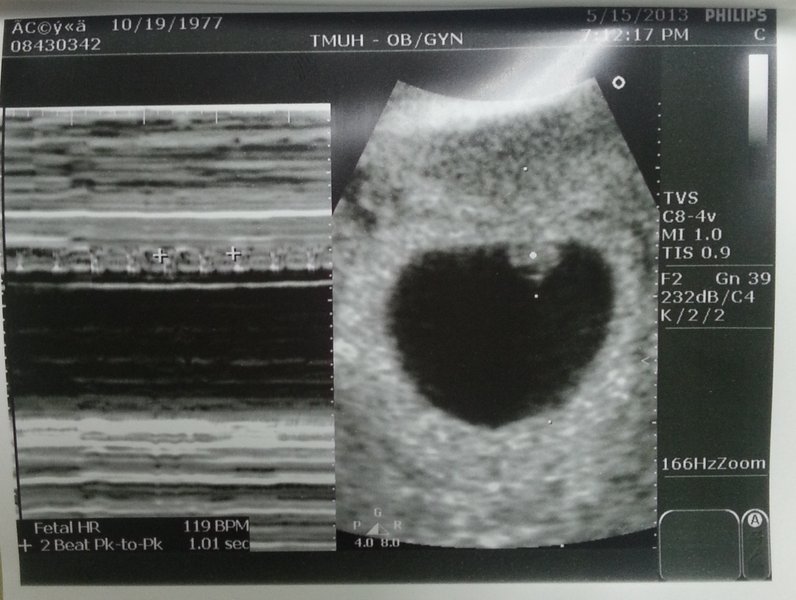

右邊是子宮內實際2D圖 有個白點跳動就是心臟的地方

針對心臟跳動 以時間為橫軸 得到的就是左邊那張